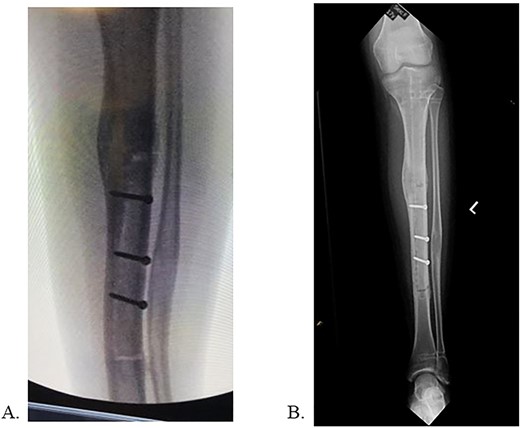

The patient was positioned supine on a radiolucent table with fluoroscopy coming from the contralateral side. The prior infrapatellar scar was incised, revealing bony ingrowth around the proximal end of the implant. A 3.2-mm guide pin was advanced into the center of the implant and a cannulated reamer removed the bony overgrowth. Residual bone surrounding the proximal implant was debrided using a bone curette and then a Nuvasive© conical extractor was attached to the exposed receiving end. The remaining proximal interlocking screw was localized under fluoroscopy and removed. When backslapping the implant, the components disassociated, and the telescopic portion remained lodged in the tibial medullary canal. When consulted intraoperatively, the mother chose to remove all implants by means of tibial osteotomy. An 8 cm long anterior ¼ circumference of the tibia unroofing osteotomy was performed using multiple drill holes and osteotomes (Fig. 2A/B). The remaining portion of the implant was removed with a clamped vice grip and mallet. (Fig. 3A/B). The osteotomy was reduced using a point-to-point reduction clamp and secured with three 2.7-mm lag by technique screws. The wound was irrigated, and 5 cc of demineralized bone matrix was applied to bolster osseous healing.

Final radiographs showed adequate alignment, internal fixation of the tibial osteotomy, and complete hardware removal aside from the three new fixation screws (Fig. 4A). The incisions were closed, dressed and the leg was immobilized in a Controlled Ankle Motion (CAM) boot. The patient spent six weeks non-weight bearing but was able to return to work without any pain or limping at three months post implant removal (Fig. 4B). Final 12-months follow-up demonstrated radiographically healed osteotomy site and maintained equal limb lengths and alignment (Fig. 5A-C).

A: Intraoperative radiograph demonstrating complete implant removal with x3 fixation screws. B: 6 weeks postoperative radiographs demonstrating maintained alignment at osteotomy site.